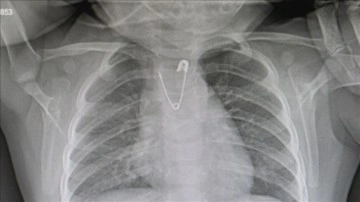

80 yaşındaki kadın sığırdan alınan kalp kapakçığı ile sağlığına kavuştu Yüksek sıcaklık ve nem uykunun "baş düşmanları" Göz altı torbalarının nedeninin sistematik hastalıklar olabileceği uyarısı Yaz dönemi artan bağırsak enfeksiyonları, çocuklar ve yaşlılarda hayati riske yol açabiliyor Kolon kanseri sonrası lösemiye yakalanan hastaya yarı uyumlu kök hücre nakledildi Vitamin, mineral ve bitkisel protein deposu: aşure Türkiye'de dumansız hava sahasının 15. yılı "Yutma riskine karşı bebeklere nazar boncuğu, kolye takılmamalı" uyarısı Bakan Memişoğlu: Sağlık sektörünü, Türkiye'nin lokomotif sektörü haline getirmek istiyoruz Çengelli iğne yutan 10 aylık bebek zamanında müdahaleyle kurtuldu DMO 8 milyon doz aşı satın alacak Kulak sağlığı için deniz ve havuzda hijyene dikkat edilmeli UNICEF, çocukların aşılanma oranındaki artışın 2023'te durduğunu açıkladı 6 günlük bebeğe "milimetrik" yemek borusu operasyonu Kalp hastası genç kadını sağlığına kavuşturan literatürlük müdahale ödül getirdi Hamilelere yazın öğle saatlerinde dışarı çıkmamaları uyarısı Temiz olmayan havuzlar Hepatit A virüsü tehlikesi taşıyor "Sıcak hava çarpması" kalp ve beyinde hasar bırakabiliyor Sağlık Bakanı Memişoğlu: Şehir hastaneleri Türkiye'nin hem gururu hem de sağlık hizmetlerinin o Araştırma: TRPC5 geni eksikliği, obezite ve doğum sonrası depresyonunu tetikliyor DSÖ, kozmetik ürünlerdeki talk mineralinin kansere neden olabileceğini bildirdi